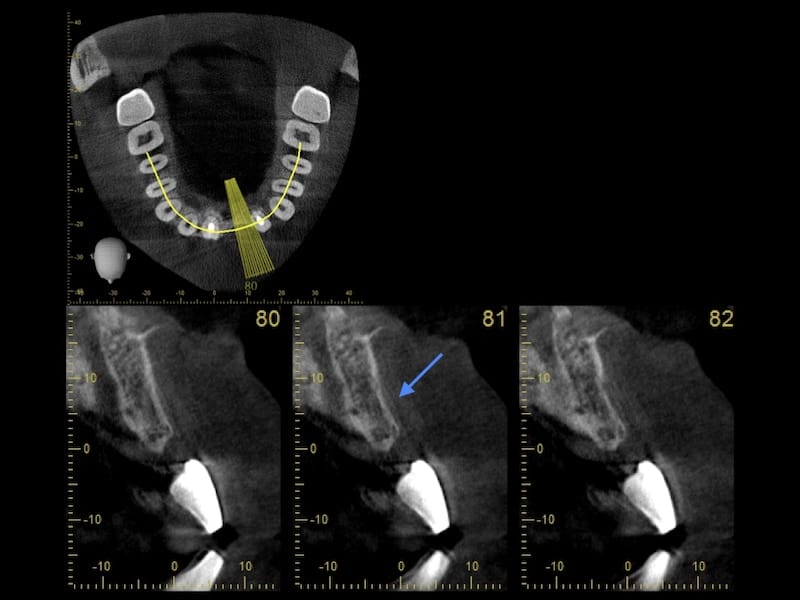

我們先治療控制牙周狀況後,開始進入利用數位電腦斷層掃描的方式,先評估他預計植牙缺牙區,齒槽骨的條件。

從電腦斷層的影像顯示,在預計要植牙的位置,齒槽骨有萎縮現象,骨頭寬度條件不足。我的治療植牙手術相關計畫是分為兩階段。第一是要先以俗稱補骨的『引導骨再生手術』,增加骨量。等待約半年的時間,在進入到第二階段,植入人工牙根。

植牙補骨前電腦斷層檢查,箭頭處顯示骨頭寬度不足

植牙補骨前電腦斷層影像 配戴手術導板拍攝植牙補骨後的電腦斷層影像,箭頭處顯示骨量有明顯變寬